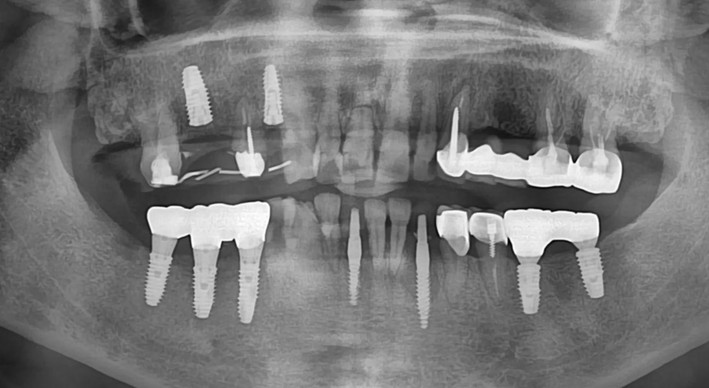

The 1-year follow-up panoramic radiograph and intraoral photograph show good maintenance with no signs of complications

The 3-year follow-up panoramic radiograph and intraoral photograph.

At the 8-year follow-up, clinical and radiographic evaluations revealed well-maintained peri-implant tissues with no signs of marginal bone loss.